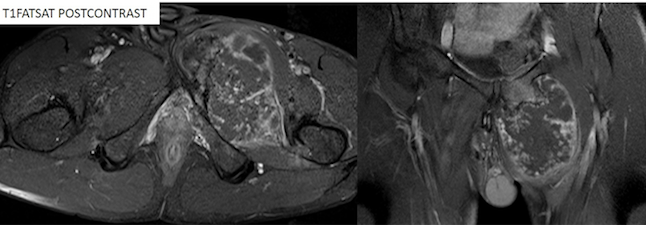

Figure 4. The lesion shows heterogeneous contrast enhancement.

MRI with and without contrast

A large intramedullary mass lesion of 9.5x8x11 cm was noted arising from the body and near portion of left superior and inferior pubic rami. The lesion appears hyperintense on T2WI, STIR and hypointense on T1WI. The lesion has a short bony stalk with direct continuation with the underlying bone.

The bulk of the tumor is noted to protrude into the medial aspect of the left upper thigh, elevating the gracilis and adductor muscle with altered signal intensity (hyperintense on T2WI, STIR) within it. On post-contrast study, the lesion shows heterogeneous enhancement.